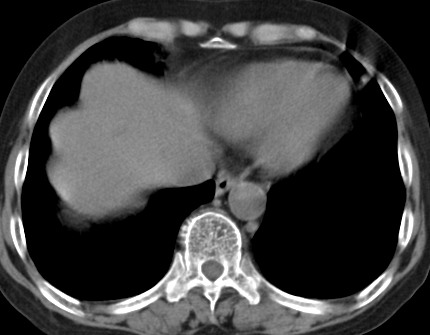

以下是引用齐原在2006-11-8 23:21:00的发言:[br]肝脏体积增大.肝表凸凹不平,肝内胆管扩张,胆总管扩张,胆总管末端突然截断,胰腺勾突增大,形态不规则.胰管扩张.考虑胰头癌.并低位梗阻性胆系扩张,胆囊炎.脾大.建议增强

以下是引用dyqct在2006-11-9 9:14:00的发言:[br]肝大,表面呈波浪状,肝内外胆管扩张,胆总管下端腔内见小结节状等密度影,胰管轻度扩张。胆囊显示不清。[br]考虑:1、胆总管下端占位性病变(等密度结石?壶腹部肿瘤?);[br] 2、肝硬化?[br] 3、建议增强扫描进一步检查。